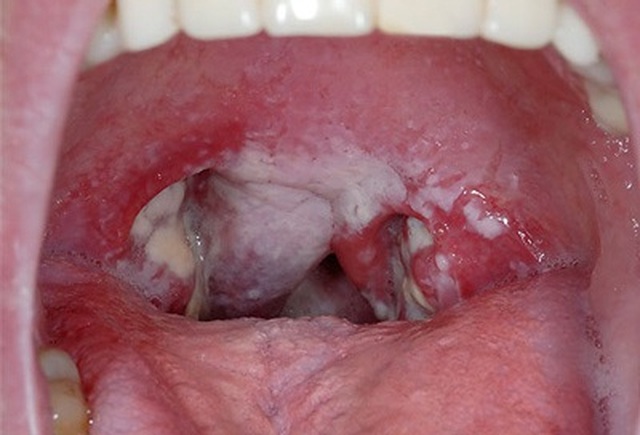

Viêm họng do liên cầu khuẩn, triệu chứng đặc trưng sẽ là nuốt đau, niêm mạc họng đỏ, có giả mạc trắng hoặc xám, sốt, ớn lạnh, chán ăn, nôn...

BS Hằng chia sẻ: “Đối với bệnh bạch cầu hạt đơn nhân có thể khiến bệnh nhân nổi hạch, đau cơ, sốt cao, ăn kém, nổi ban đỏ. Trong khi đó, với viêm họng do liên cầu khuẩn, triệu chứng đặc trưng sẽ là nuốt đau, niêm mạc họng đỏ, có giả mạc trắng hoặc xám, sốt, ớn lạnh, chán ăn, nôn…”.